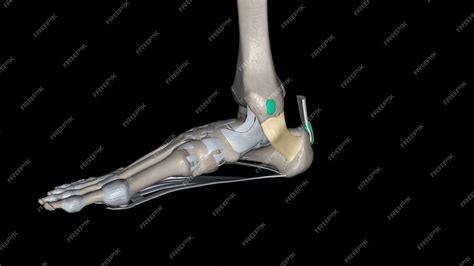

Beneath the flexor retinaculum lies the tarsal tunnel, a narrow space through which several vital components pass. If the retinaculum becomes thickened or inflamed, it can compress these structures, leading to discomfort. The following structures pass through this passage, often remembered by medical professionals via specific mnemonics:

• Tibialis Posterior Tendon: Located most anteriorly, essential for supporting the arch of the foot.

• Flexor Digitorum Longus Tendon: Responsible for curling the toes.

• Posterior Tibial Artery and Veins: Provide essential blood supply to the foot.

• Tibial Nerve: The primary nerve providing sensation to the sole and motor function to foot muscles.

• Flexor Hallucis Longus Tendon: Positioned most posteriorly, responsible for flexing the big toe.